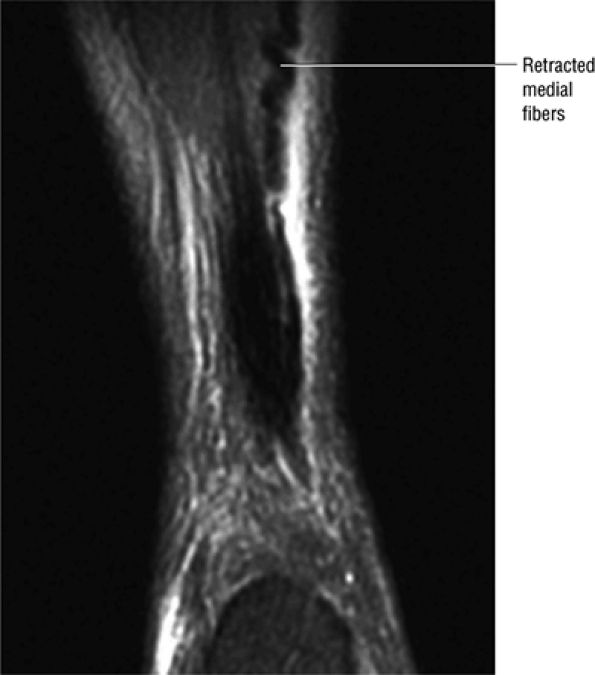

FIGURE 5.123 ● Partial Achilles tendon tear with the “corkscrew” morphology of partially retracted fibers. Coronal FS PD FSE image.